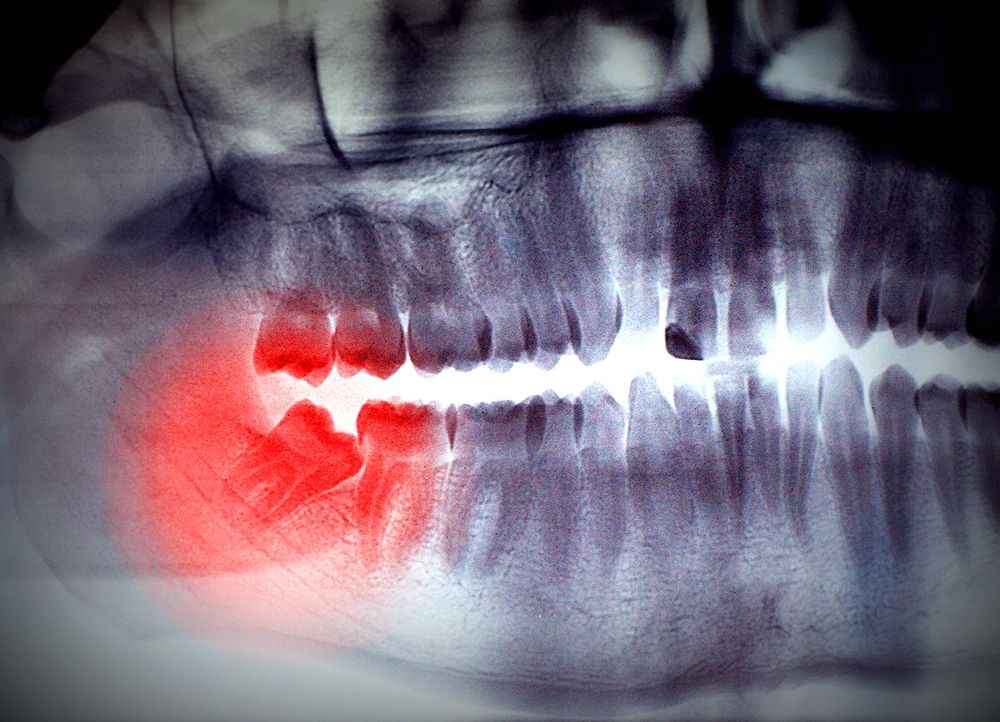

Panoramic Dental XRay Before Orthodontic Treatment With Bud Of Wisdom Wisdom Teeth And Orthodontic Treatment Should i be worried about. Wisdom tooth extraction, also called removal, is a surgical procedure to take out one or more wisdom teeth. In some cases, wisdom teeth have no impact on orthodontic treatment, and the specialist might even cement braces on them. In this blog we’ve answered all common questions about wisdom teeth before in relations to orthodontic treatment. Wisdom Teeth And Orthodontic Treatment.